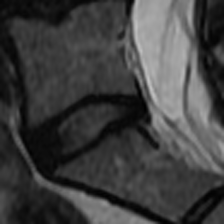

Lumbar Disc Degeneration (LDD) was found to be one of several reasons causing Low Back Pain [1]. Although there are several grading systems to quantify LDD, the Pfirrmann and Schneiderman scales are commonly used [2]. Pfirrmann et al. proposed a 555-scale grading system using T2-weighted MR imaging [3]. The grading system uses an algorithmic approach for LDD using signal intensity and disc homogeneity, demonstrated in Fig. 1. Over the past few years, several Deep Learning based methods were built to quantify LDD using MR imaging and the Pfirrmann grading system.

(a) PG 2

(b) PG 3

(c) PG 4

(d) PG 5

Fig. 1: Pfirrmann grades in L5-S1 as graded in the Northern Finland Birth Cohort dataset